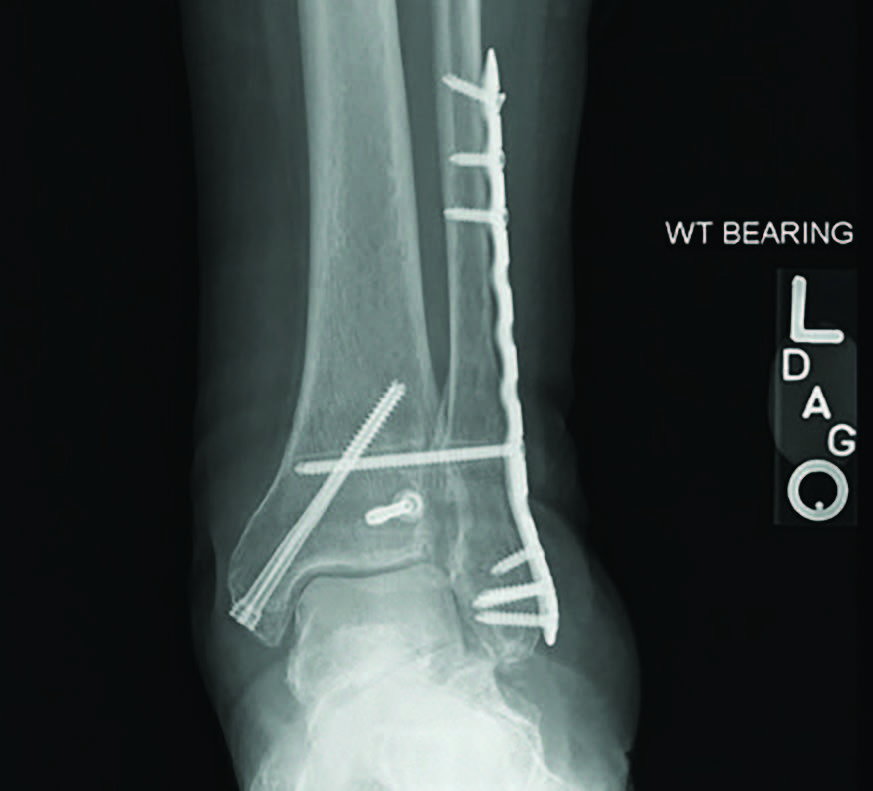

I would like to present a case of a 72-year-old female with osteoporosis, a history of chemotherapy and previous tobacco use over 10 years ago. She previously sustained a closed trimalleolar ankle fracture, which I reduced and fixated appropriately with plates and screws. The patient diligently followed the postoperative course despite being a caretaker for her husband and the fracture had healed a year prior to her current presentation. However, she is now presenting with continued pain and disability.

Radiographs demonstrated a subtalar joint dislocation with advanced degenerative changes (see first two images above). As we prepared for a subtalar joint fusion, we emphasized medical optimization of her vitamin D levels and made sure to rule out any metabolic weaknesses that would alter our techniques in the operating room. In my experience, it is best to perform these complex cases at facilities that can provide comprehensive patient care and possible admission if necessary.

For this patient, I ultimately performed a subtalar joint fusion with distal tibial autograft. She subsequently went on to develop a symptomatic non-union at six months postoperatively and collapse of her talus (see third image above). She again had medical optimization and we planned for a femoral head allograft reconstruction with Augment bone graft and intramedullary nail fixation. The patient went on to clinical success and there was demonstrated healing on a CT scan at four months post-op. She is now weightbearing in a shoe at two years post-op (see fourth and fifth images above).